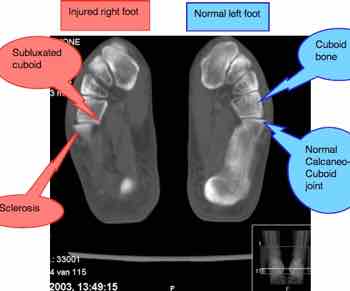

Carefully compare the cuboid ankle bones on the right and the left. Can you see how the cuboid has subluxated in her right foot? Note also the sclerosis forming there too - that's the beginning of immobilisation arthritis forming in the calcaneo-cuboid joint, and this CT was taken when she was only 30 years old. Can Chiropractic help ankle joint pain?